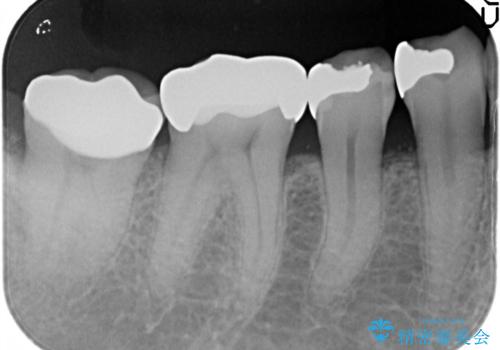

セラミッククラウンによるむし歯治療

- 他院で入れたセラミックインレーがかけたことを主訴に来院されました。

他の部位にもむし歯を認めたため、優先度の高い歯から治療を行っております。

咬合力が強くかかる部分には欠けるリスクのほとんどない金属を用いることが最良ですが審美性に劣ります。

今回は白い材料での修復を希望されたため、欠けるリスクが高いセラミックインレーは避け、セラミッククラウンにて治療を行いました。